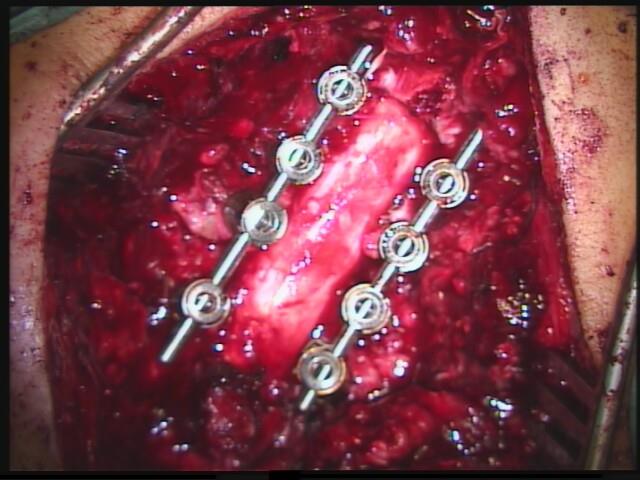

Versteifung der Halswirbelsäule von ´hinten´:

Bei langstreckigen Verengungen des Rückenkanals muß das Rückenmark wieder Platz bekommen. Dies gelingt in seltenen Fällen nur durch eine knöcherne Öffnung des Spinalkanals von hinten. Dazu ist eine Versteifung der Wirbel mit einem Schrauben-/Stangensystem erforderlich. Das ist in diesen Fällen die einzige Möglichkeit, einer Zunahme eines Rückenmarksschadens mit Querschnittssymptomen vorzubeugen. Diese Operation führe ich in Diez gemeinsam mit Prof. Schönmayr durch.